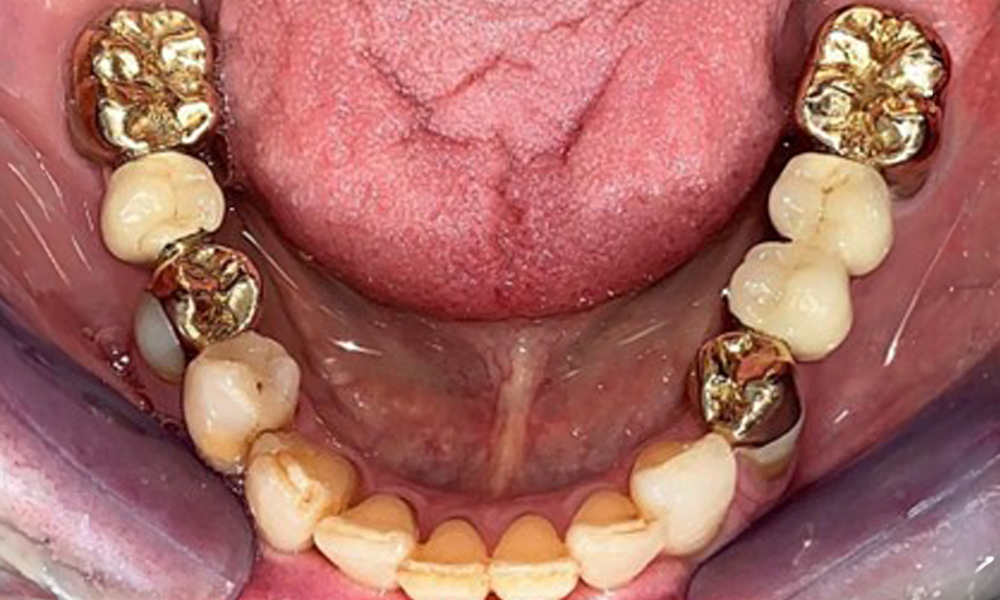

Okklusalansicht Unterkiefer

Abb. 4: Okklusalansicht Unterkiefer

Der dentale Befund stellt sich wie folgt dar: Kombinierte herausnehmbare Implantat- und zahngetragene Teleskoparbeit auf Implantaten 15, 13, 21, 23, 24, 25 und Zahn 11 (Abb. 1, Abb. 2, Abb. 3). Im Unterkiefer ist die Patientin mit einem festsitzenden Zahnersatz versorgt. 37–34 sowie 45–47 haben suffiziente Brücken (Abb. 4). Kronenränder sind intakt, aktive kariöse Läsionen sind nicht vorhanden. An Zahn 43 zeigt sich eine Compositefüllung mit Randspalt. Im Unterkiefer liegen Rezessionen mit freiliegender Wurzeloberfläche zwischen 1 – 3 mm vor. Dies trifft auch für 11 zu.